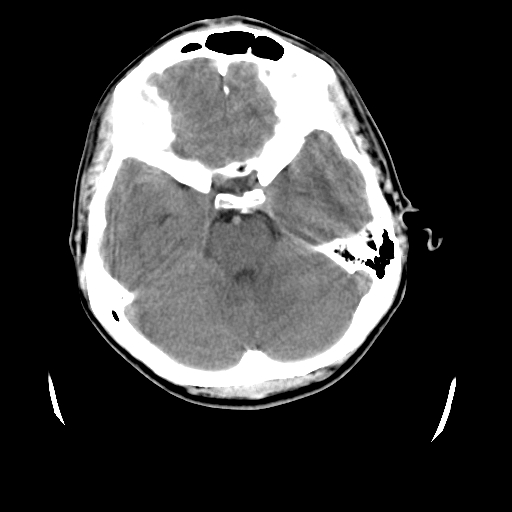

标题: CT23601:男, 17岁,剧烈头痛一小时。 [打印本页]

标题: CT23601:男, 17岁,剧烈头痛一小时。

男, 17岁,剧烈头痛一小时。